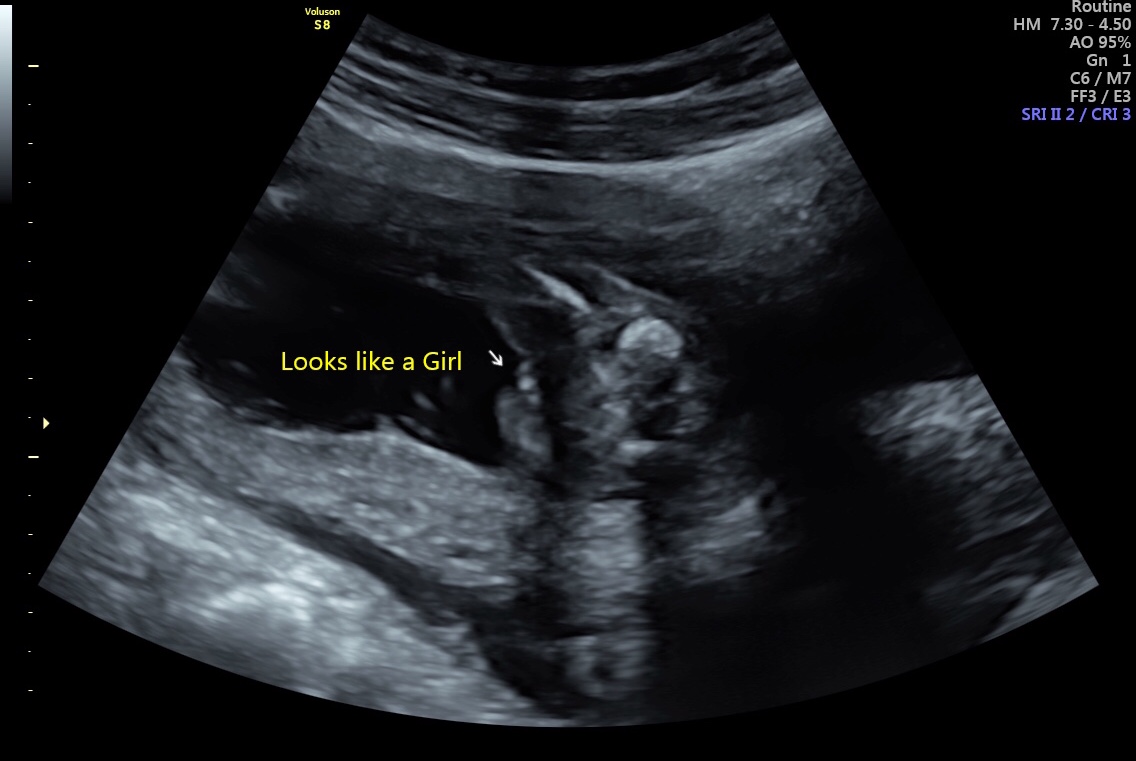

We had our 16 week ultrasound a few weeks ago and I keep worrying that the sonographer might have got it wrong. We got lots of pictures. Some look girly and others I’m not so sure. What do you all think? Attachment 39988

Yes looks like a girl. Congrats!

Girl!